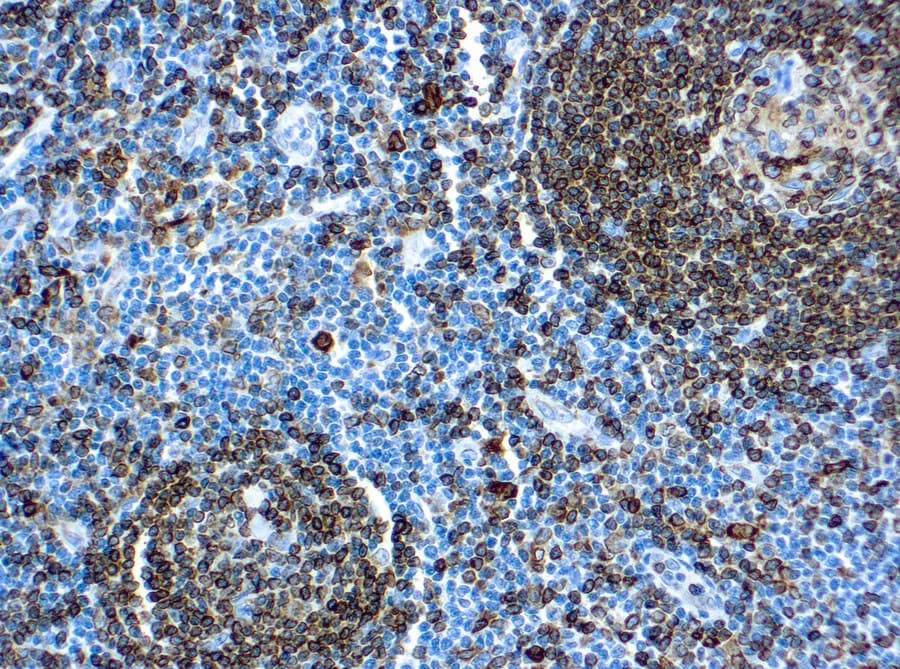

- Muestran una tinción membranosa y citoplasmática consistente con el tráfico intracelular de CD74.

- Proporcionan una detección sensible de las células presentadoras de antígenos y de los compartimentos ricos en células B.